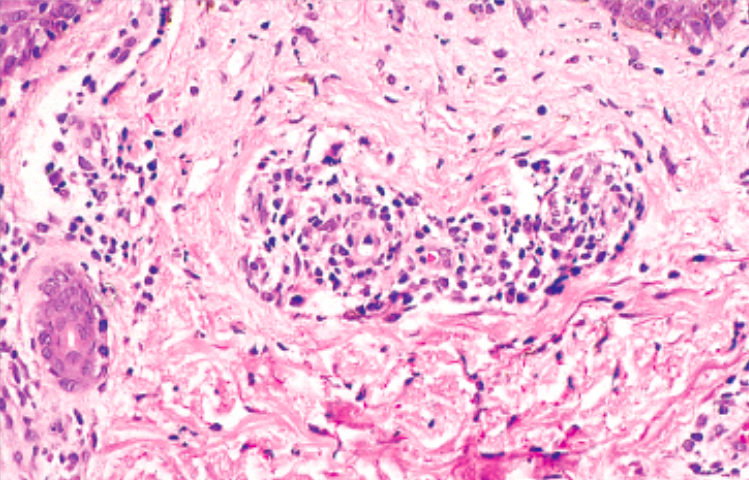

This patient presented with diarrhea, bloating and malabsorption. GI biopsy is shown below. What is the life cycle of this organism?

Strongyloides infects through the skin, goes through the lungs and into the GI tract. It is the only parasite that can complete its lifecycle in humans. It can go on to disseminate to the brain, liver and kidneys in immunosuppressed patients, especially when they are given corticosteroids.